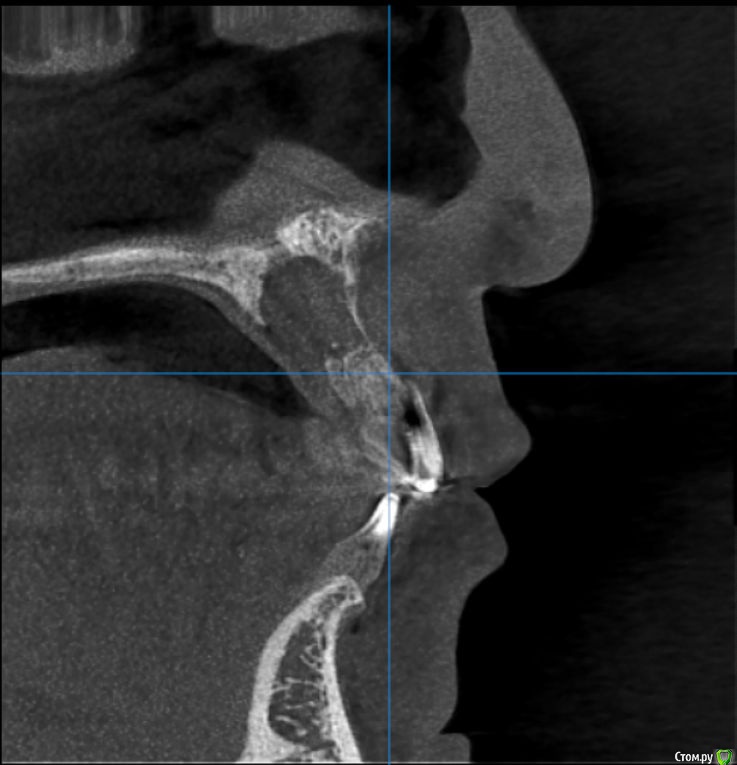

Kazankov.Egor Опубликовано 6 июля, 2018 Поделиться Опубликовано 6 июля, 2018 (изменено) Жалобы на неприятный запах изо рта, предположительно от 11 зуба. В анамнезе РВК 11 зуба.Скрины кт прилагаю. Пациент девушка, естественно, главный вопрос -эстетика. Нужна помощь по тактике. Изменено 6 июля, 2018 пользователем Kazankov.Egor Ссылка на комментарий

Kazankov.Egor Опубликовано 7 июля, 2018 Автор Поделиться Опубликовано 7 июля, 2018 Если зуб под коронкой не сгнил, то ревизия периапикальных тканей и ретроградная пломбировка канала.А с кистой несонобного канала как поступить? Ссылка на комментарий

Kazankov.Egor Опубликовано 7 июля, 2018 Автор Поделиться Опубликовано 7 июля, 2018 При такой тактике не потеряю ли я объем в области кисты? Если сыпать графт, не будет ли повышенного риска его инфицирования? Нужно стабилизировать графт мембраной? Ссылка на комментарий

АнтонТЛТ Опубликовано 7 июля, 2018 Поделиться Опубликовано 7 июля, 2018 Я графт не использую при резекциях. Само восстановится. 1 Ссылка на комментарий